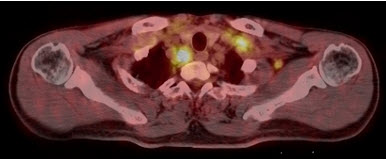

Hình 1. Bệnh nhân Vũ D.L., nam, 56 tuổi. Chẩn đoán: Non Hodgkin Lymphoma , GPB: WF7. Hình PET/CT toàn thân thấy tổn thương hạch ở nhiều vị trí: vùng cổ, trung thất, hố nách, ổ bụng, bẹn (các mũi tên) tăng hấp thu FDG.

Hình 2. Bệnh nhân Trần V. V., nam, 57 tuổi. Chẩn đoán: u lympho hốc mũi; Giải phẫu bệnh: WF5. Hình CT, PET và PET/CT cho thấy tổn thương u ở vùng hốc mũi trái (mũi tên) tăng hấp thu FDG.